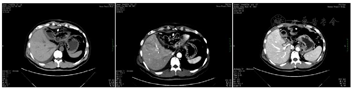

患者术后恢复良好,2022年5月15日复查CT:左半肝及原肿块已切除(图5),术区见少量积液积气,左膈部分切除,胆囊切除,胆肠内引流术后,肝内胆管未见扩张,门静脉右支局部变窄。于5月20日术后10 d出院。术后继续使用原方案综合治疗,于2022.5.30给予输注派安普利单抗200 mg,2022年6月7日恢复口服盐酸安罗替方案(12 mg,1次/d,2周停1周),患者目前各项指标正常。